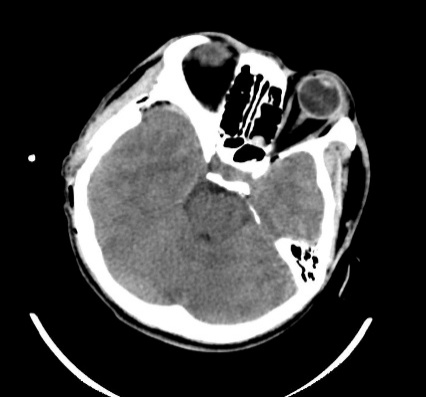

2.1. Xử lý hiệu quả các ca chấn thương sọ não: điều trị các ca chấn thương sọ não nặng Phẫu thuật các loại máu tụ nội sọ: ngoài màng cứng, máu tụ dưới màng cứng, máu tụ trong não,…

2.2. Xử lý các trường hợp đột quỵ não cấp: Phối hợp với các khoa liên quan để điều trị toàn diện. Phẫu thuật lấy máu tụ hoặc mở sọ giải áp khi có chỉ định các ca xuất huyết não, nhồi máu não,…

Phẫu thuật lấy máu tụ nội sọ